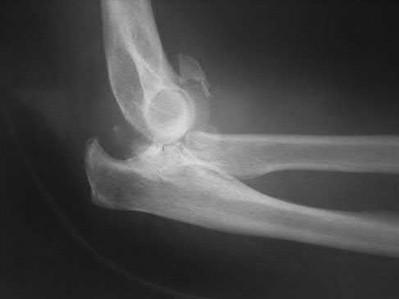

A 72-year-old woman falls down stairs and sustains the injury shown in Figure A. Additional radiographs are performed in Figure B to help assess the fracture pattern. These additional radiographs represent which of the following?

Additional traction radiographs are performed in distal humerus fractures to better understand the fracture configuration.

Traction radiographs help align the fracture fragments for better visualization. This is useful in comminuted fractures where distal fragments are telescoped or flexed on the proximal fragments, making CT scan visualization difficult.

Proper visualization can help determine (1) the approach to the distal humerus, (2) whether to perform ORIF or total elbow arthroplasty (in select patients), (3) whether to add a 3rd plate (lateral column), (4) whether to add tricortical bone graft to augment distal fixation and restore trochlear width.

Figures A and B show a distal humerus fracture without traction (A) and with traction (B) applied. Illustration A shows the same fracture after bicolumnar plating. Illustration B shows the different surgical approaches to the distal humerus (A, Campbell triceps splitting; B, O'Driscoll triceps reflecting anconeus pedicle [TRAP]; C, Bryan-Morrey triceps reflecting; D, olecranon osteotomy)